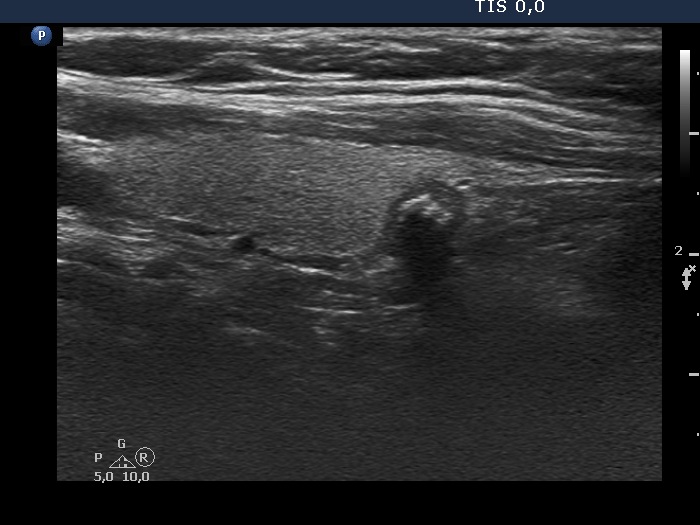

The borders of the nodule - case 2109 (ultrasonographic picture 5)

Lower part of the right lobe, longitudinal view. Based on the acoustic shadow, the lesion has macrocacifications, as well.